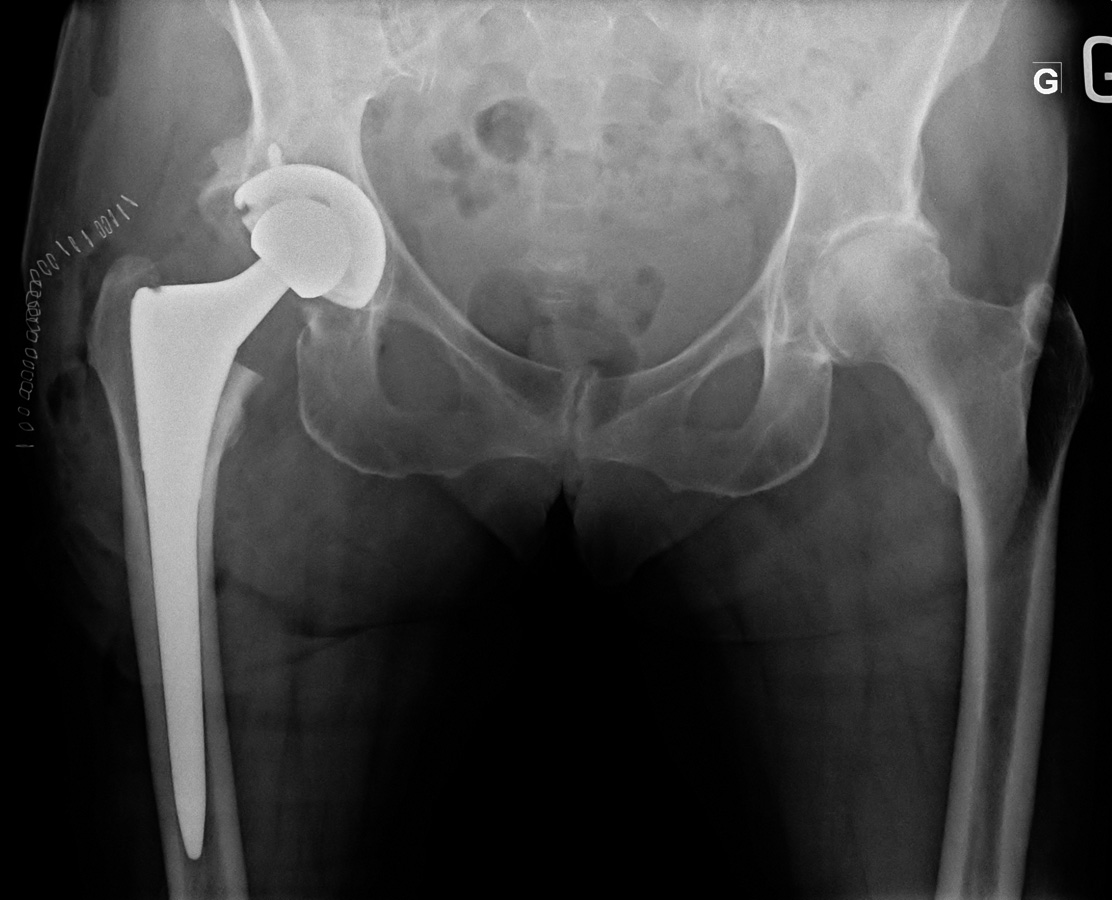

82-year-old female:

Postoperative control of a total hip arthroplasty.

Right total hip replacement. The femoral component is uncemented and has a press-fit fixation.

The acetabular component is held by press-fit and one screw in the pelvis.

Metallic staples for surgical wound closure.

Preservation of the length of the operated leg can be assessed by drawing a line along the ischial tuberosity and measuring its distance to the lesser trochanter. Here, this distance is the same on both sides.

The acetabular component abduction can also be measured, here at 40°. This is the target perioperative value.